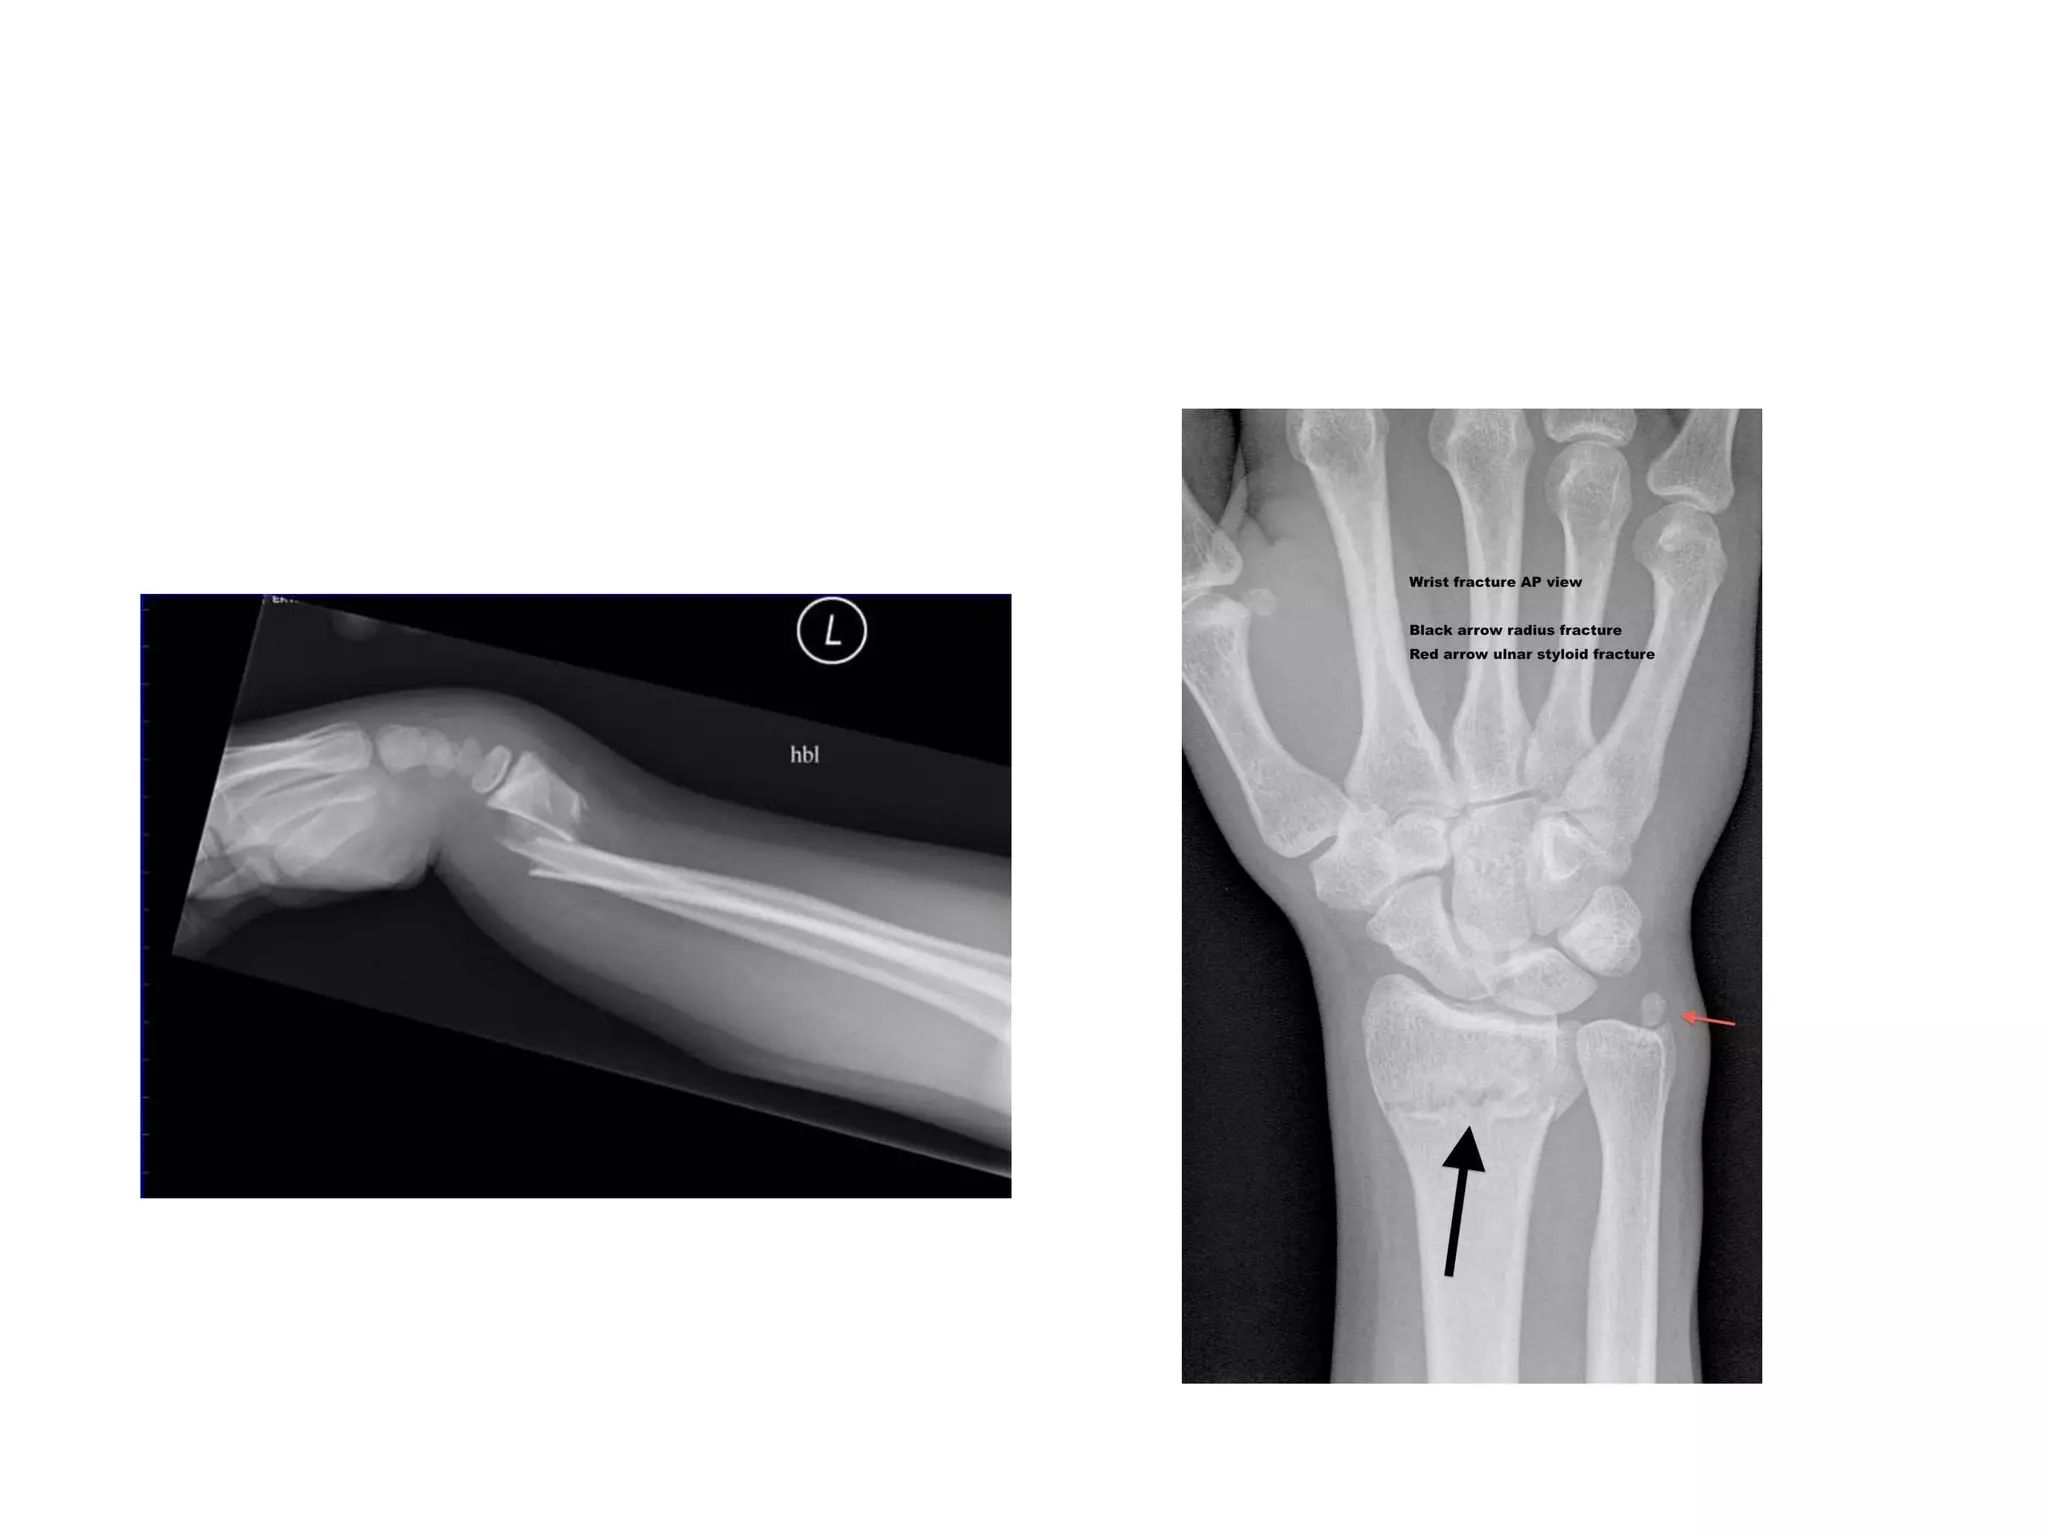

Radiological features: (Differentiated from

other fractures at the same site by looking at

the displacements)

oDorsal tilt can be detected on a lateral

X-ray:

 normal  faces ventrally

 dorsal tilt  faces dorsally or becomes

neutral

oLateral tilt can be detected on an AP X-

ray:

 normal  faces medially

 lateral tilt  faces laterally or becomes

horizontal

Clinical features: oPain oSwelling oDeformity ofthe wrist oOn examination;  Tenderness  Irregularity of the lower end of radius Radiological features: (Differentiated from other fractures at the same site by looking at the displacements) oDorsal tilt can be detected on a lateral X-ray:  normal  faces ventrally  dorsal tilt  faces dorsally or becomes neutral oLateral tilt can be detected on an AP X- ray:  normal  faces medially  lateral tilt  faces laterally or becomes horizontal

• #15 Fall on extended hand colles…fall on flexed hand smiths

• #19 Lateral view for dorsal displacement & AP view for lateral displacement

• #20 Slight flextion,pronation & ulnar deviation…

• #21 Fall on back-dorsum of hand